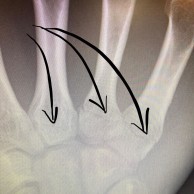

La ciclista Annika Langvad acaba de confirmar que se ha fracturado la mano y se ha fisurado el omóplato en una carrera local de MTB, categoría C1. Esta lesión no hace más que empeorar las cosas para la danesa, que hasta ahora no estaba teniendo un gran inicio de Copa del Mundo.

Ella misma ha confirmado que esta fractura le hará llevar la mano inmovilizada durante 4 semanas lo que le dificultará su preparación para la próxima Copa del Mundo en Vallnord.

"Hasta ahora no podía decir que mi temporada de MTB de primavera hubiera ido sobre ruedas. Hoy me caí durante el calentamiento en una carrera local de C1 y me rompí al menos dos huesos en mi mano derecha más una pequeña fractura en el omóplato. Esto me obligará a estar 4 semanas con un yeso, pero debería poder subirme al rodillo y a la bicicleta de carretera mientras tanto. ¡Qué fastidio!"